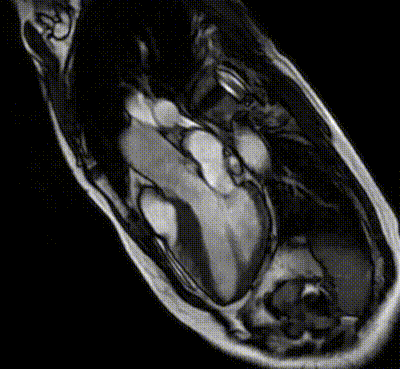

(三腔心电影序列)